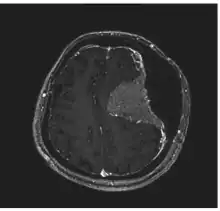

Image revealed a bilateral frontoparietal bone hyperostosis, particularly in the left side -

Meningioma of the middle third of the sagittal sinus with large hyperostosis